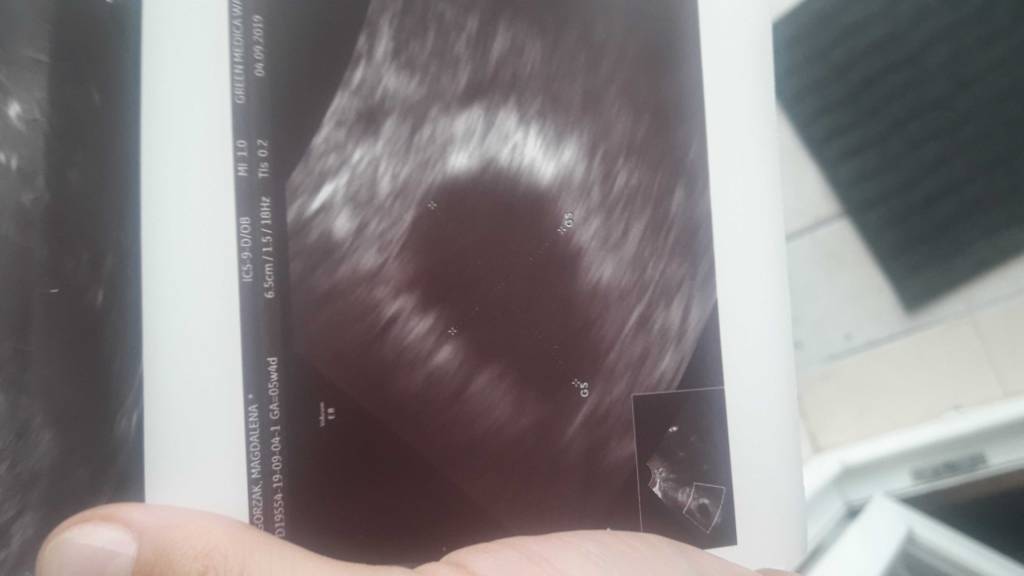

Liczony wg miesiączki 5 tydzień 4 dni.Super. A który to tydzień?

u mnie byl 5+4 i byl wodac peherzyk 8x13mm ale nie bylo jeszcze zarodka.a ktory tydz?

Myślę, że na następnej wizycie zobaczysz już więcej. Kiedy masz kolejny termin?u mnie byl 5+4 i byl wodac peherzyk 8x13mm ale nie bylo jeszcze zarodka.

Wyszłam od lekarza z uśmiechem na ustach jest pęcherzyk i ciałko żółte! Wierzę, że w tej ciąży będzie wszystko dobrzeTeraz 3 tygodnie zwolnienia do kolejnej wizyty.